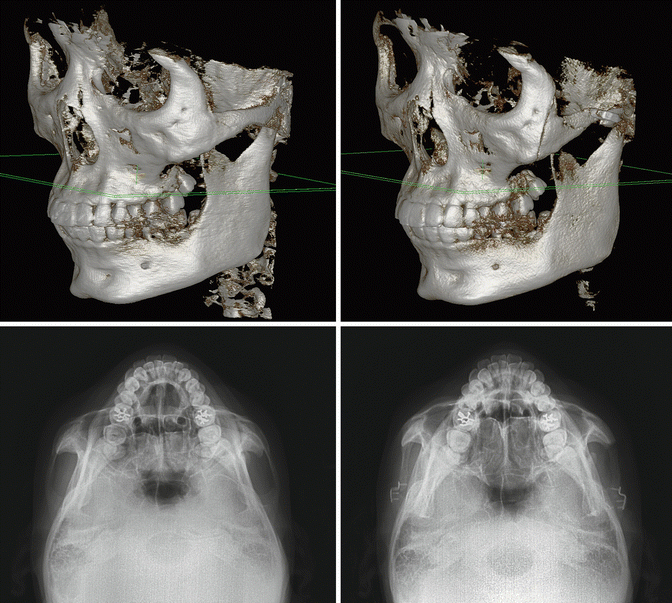

Fig. 19.2

Comparison on preoperative and postoperative imaging studies. Preoperative and postoperative three-dimensional computed tomographic images (above). Preoperative and postoperative zygomatic arch view radiographs (below)